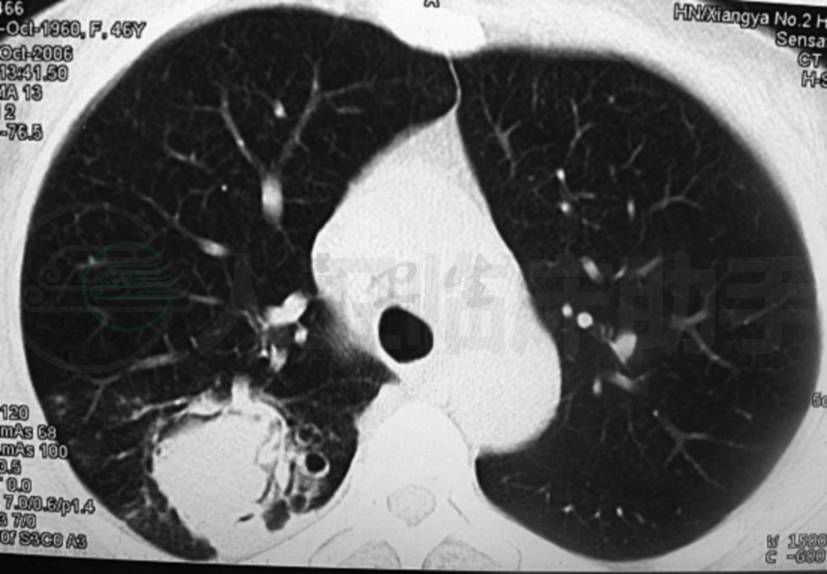

患者,女性,48岁,农民,因咯血伴胸痛8年,加重1周,于2007年12月31日入院。患者诉8年前无明显诱因出现咯血,为鲜红色,量不多,伴右侧胸背部隐痛,无咳嗽、咳痰、发热等不适,遂入当地医院就诊,予以“止血、抗感染”等对症支持处理后病情好转。但之后患者病情反复发作,于2000~2001年在外院行规律抗结核治疗1年,后又间断行抗结核治疗,病情无明显好转。1年前,患者咯血量增多,发作较前频繁,在外院查肺部CT(图1)示右上肺斑片影,其周可见大小不一囊性空洞,考虑:①结核;②多发性肺囊肿并感染。至我院行支气管镜检查示支气管化脓性炎症,遂间断抗感染治疗。1周前,患者咯血量增多,为鲜红色,约30ml/d,伴胸痛,为求进一步诊治入我院。患者本次起病以来,精神、食欲欠佳,二便正常,体重亦无明显变化。

图1 肺CT(2006-12-12)